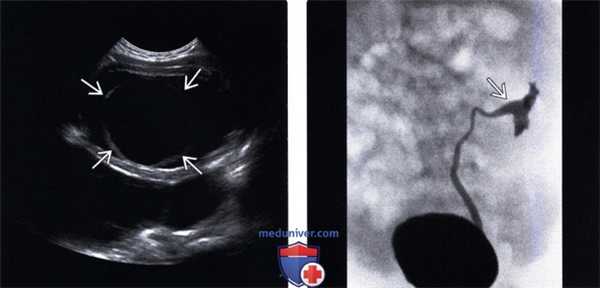

(Левый) На продольном ультразвуковом срезе удвоенной левой почки визуализируются диспластические кистозные изменения верхней лоханки.

(Правый) На поперечном ультразвуком срезе мочевого пузыря визуализируется расширенный левый мочеточник, который отходит от удвоенной левой почки, и прикрепляется с образованием крупного уретероцеле.

(Левый) На трансвагинальном ультразвуковом срезе визуализируется толстостенный инфицированный мочеточник со взвесью в просвете рядом с неизмененным левым яичником. Его можно ошибочно принять за пиосальпинкс, однако строение и ход мочеточника отличаются.

(Правый) На фронтальном Т2 HASTE МР-срезе визуализируется расширенный левый мочеточник, впадающий во влагалище ниже шейки мочевого пузыря. Верхняя лоханка удвоенной системы значительно расширена. Мочевой пузырь не изменен.

(Слева) УЗИ мочевого пузыря в продольной плоскости: извитой расширенный мочеточник, продолжающийся вне ожидаемого отверстия в треугольнике мочевого пузыря.

(Справа) УЗИ в продольной плоскости: у этого же пациента определяется кистозное образование в стенке влагалища, представляющее собой эктопическое устье расширенного и закупоренного мочеточника, дренирующего верхнюю лоханку удвоенной собирательной системы. Также визуализируется матка, которая имеет нормальные характеристики.